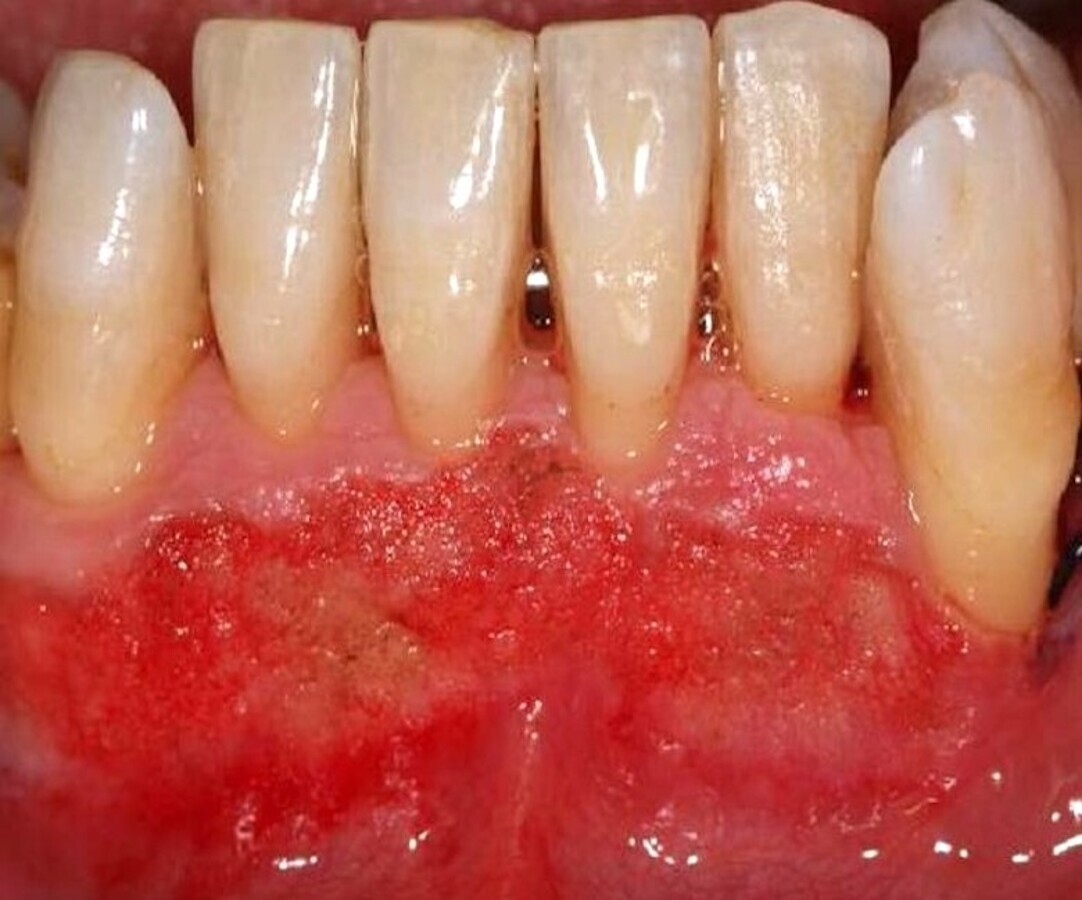

El tratamiento de estas pigmentaciones con el láser de diodo obtiene buenos resultados a nivel estético, es cómodo para el paciente durante y después de la intervención, y los resultados son muy estables a lo largo del tiempo (Figuras 6-8).

El láser de diodo obtiene buenos resultados estéticos en el tratamiento de pigmentaciones (ver Figuras 6-8).

Figura 6.

Figura 7.

Figura 8. Las figuras 6-8 muestran el tratamiento de las pigmentaciones con el láser de diodo obtiene buenos resultados a nivel estético y es cómodo para el paciente.